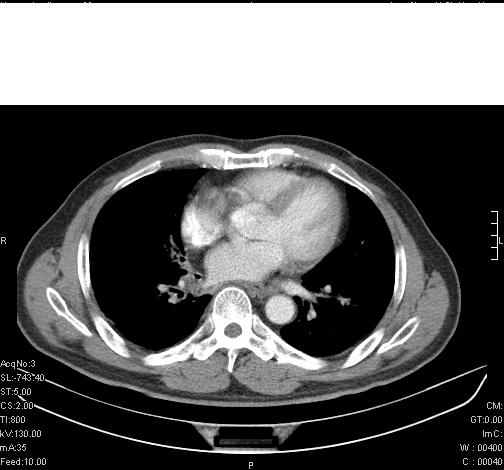

标题: CT6685:右肺阻塞性炎症,增强CT。

前几天,发了患者的平扫片,患者抗炎一周后增强扫描。右中叶病灶吸收明显,但下叶病灶未见明显吸收。右肺门可见结节影,看来凶多吉少

右肺下叶支气管管腔狭窄,管壁增厚,右下肺见斑片状高密度影,考虑右侧肺门中心肺癌伴阻塞性肺炎

右肺下叶支气管壁明显增厚,考虑癌症并阻塞性炎症、肺门淋巴结肿大

考虑右肺癌并阻塞性炎症、肺门淋巴结肿大

右肺下叶支气管壁不规则增厚,右肺下叶有斑片状影分布。考虑右肺中央型肺癌伴右肺下叶阻塞性改变。建议支纤镜检查。平扫比增强较好显示了病变情况。

右主支气管狭窄,管壁增厚。考虑右中心性肺ca伴阻塞性肺炎。

既然抗炎治疗有效,可继续治疗;右肺下叶支气管管腔狭窄,管壁增厚,右下肺见斑片状高密度影,右侧主支气管后见结节影(淋巴结?),肺癌不能排出。